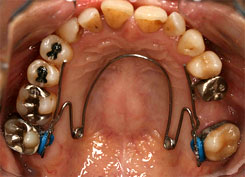

リンガルアーチ・ツインヘリックス・TPA

歯の裏側にワイヤーを沿わせ、歯列を拡大したり、歯軸を動かしたりする矯正装置です。

●リンガルアーチ

装着時 5ヶ月後

●ツインヘリックス

装着時 1ヶ月後